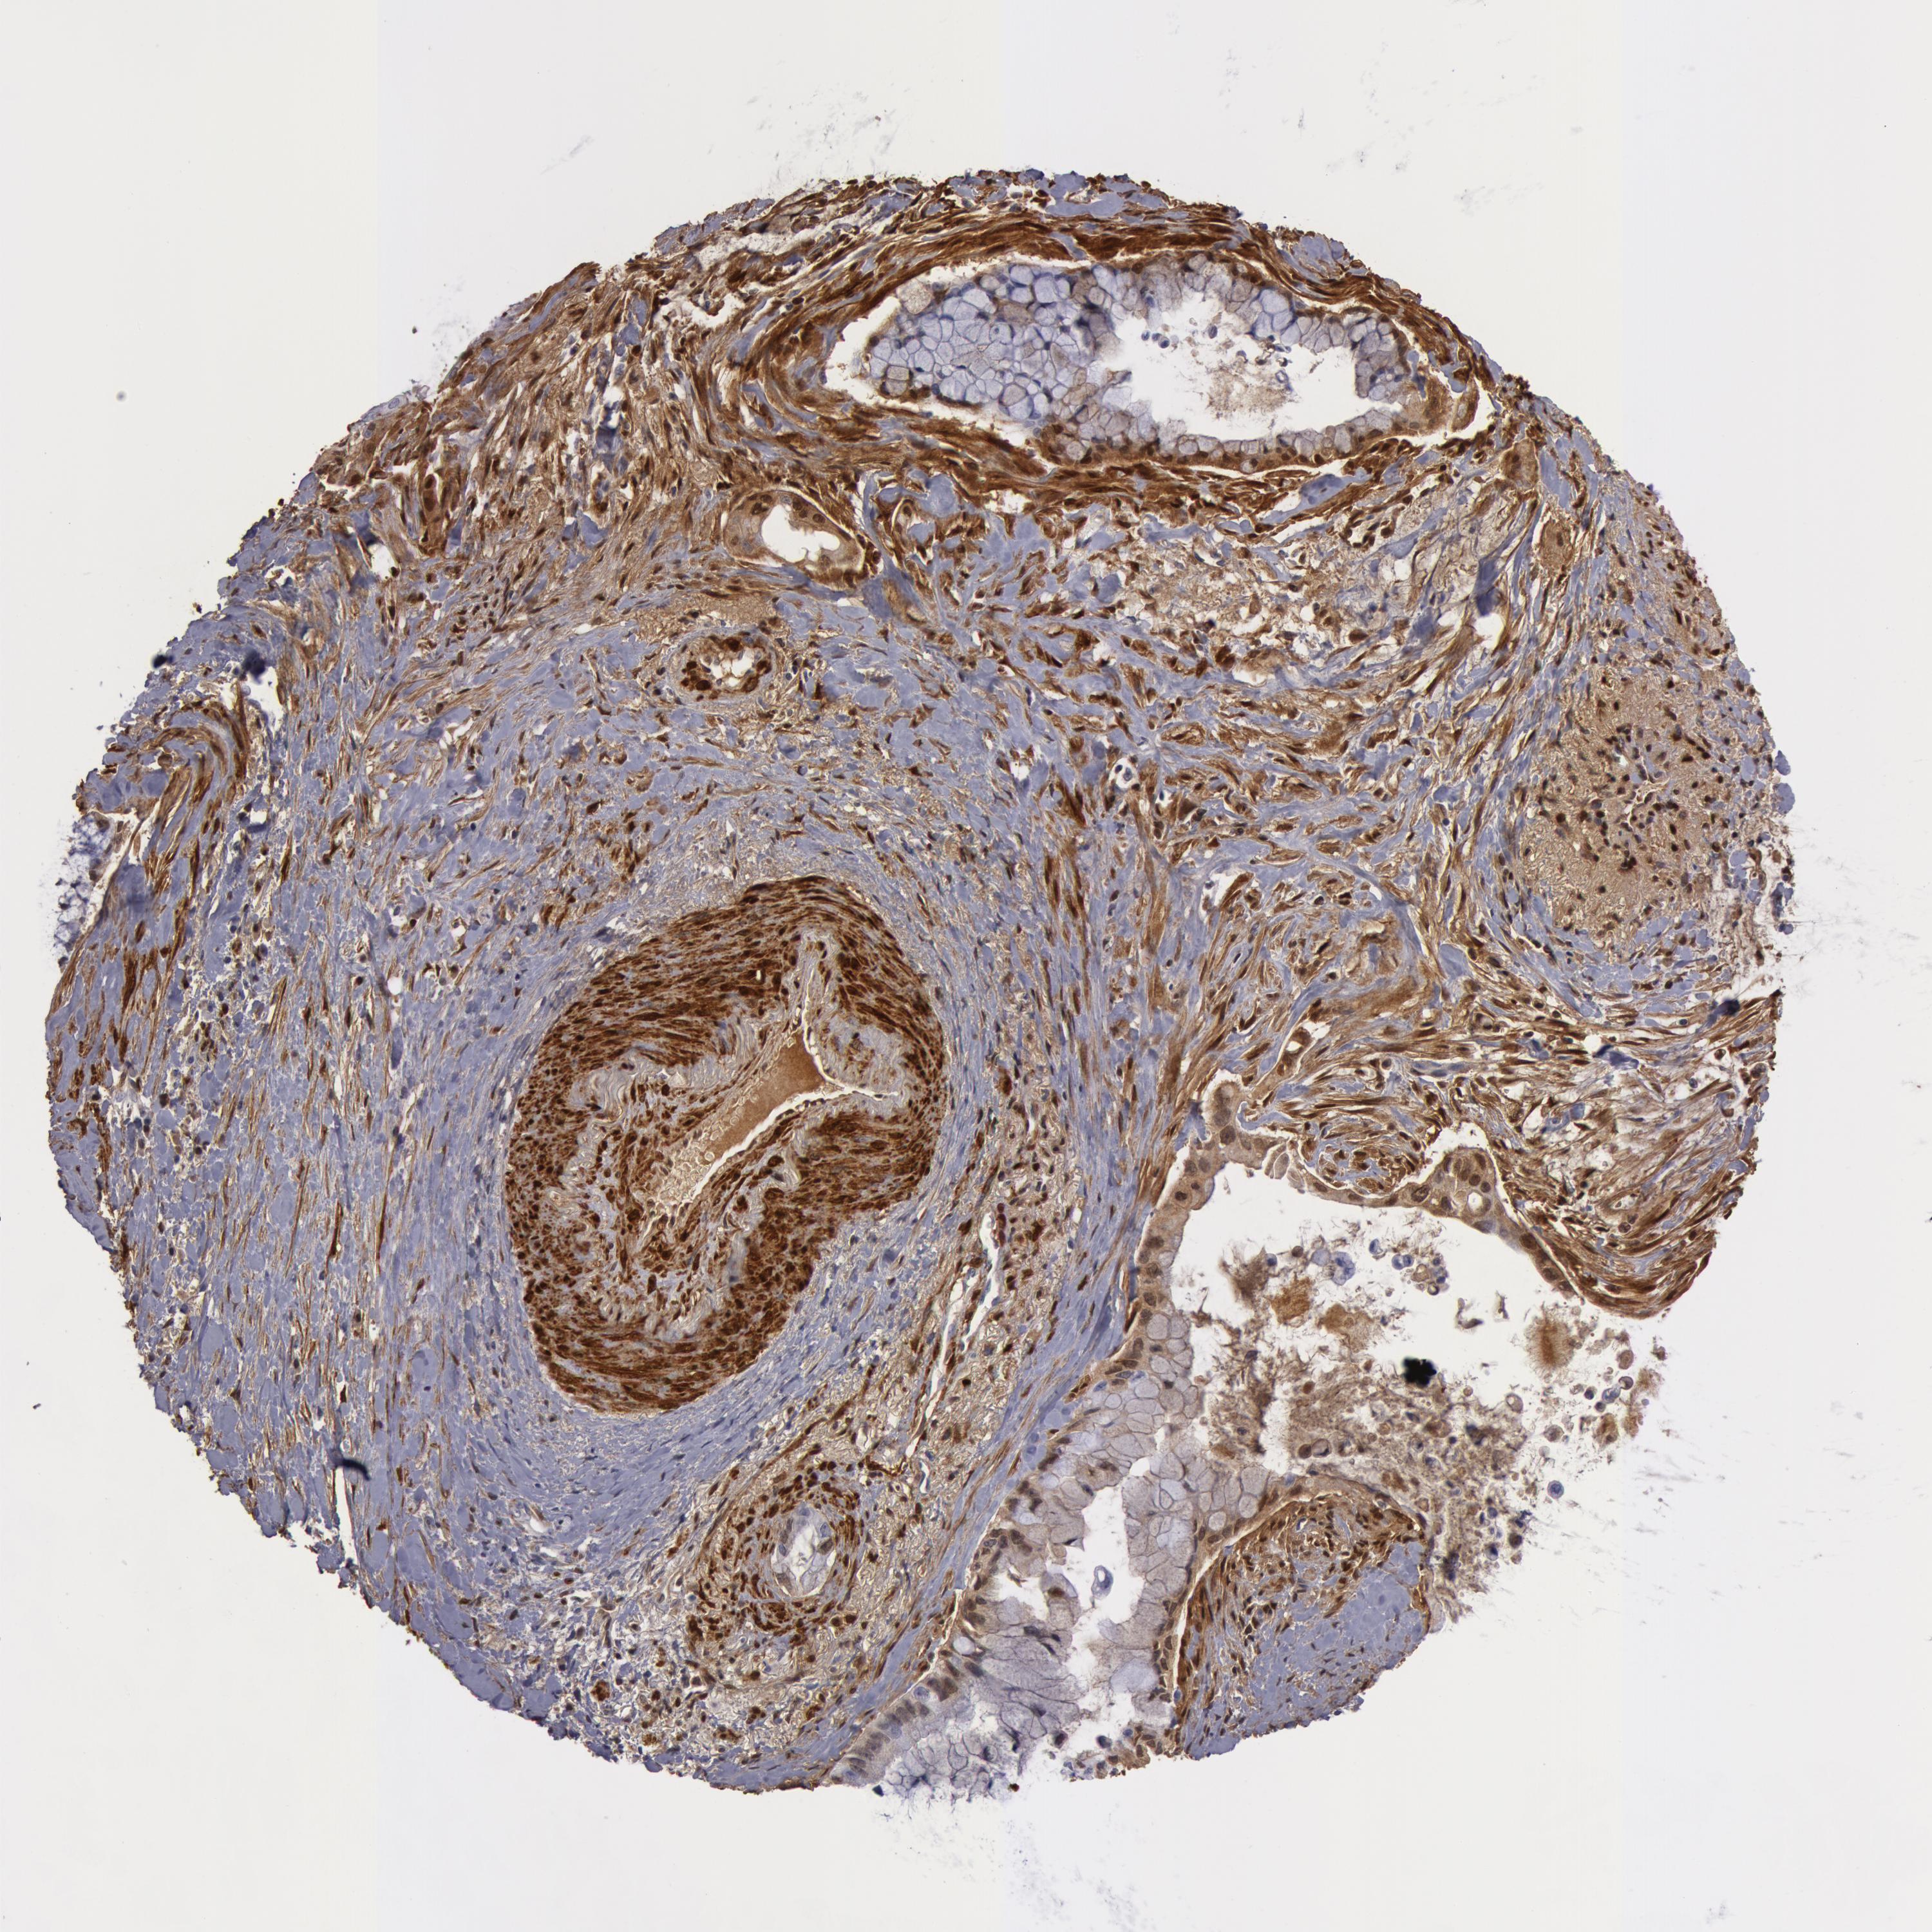

PANCREATIC CANCER - Protein expressioni

A mouse-over function shows sample information and annotation data. Click on an image to view it in a full screen mode. Samples can be filtered based on level of antibody staining by selecting one or several of the following categories: high, medium, low and not detected. The assay and annotation is described here.

Note that samples used for immunohistochemistry by the Human Protein Atlas do not correspond to samples in the TCGA dataset.

Antibody stainingi

Antibody staining in the annotated cell types in the current human tissue is reported as not detected, low, medium, or high, based on conventional immunohistochemistry profiling in selected tissues. This score is based on the combination of the staining intensity and fraction of stained cells.

Each image is clickable and will lead to virtual microscopy that enables deeper exploration of all samples and also displays staining intensity scores, fraction scores and subcellular localization as well as patient and tissue information for each sample.

Antibody HPA019467

Antibody HPA061657

Antibody CAB001447

Staining

High

Medium

Low

Not detected

Intensity

Strong

Moderate

Weak

Negative

Quantity

>75%

75%-25%

<25%

None

Location

Nuclear

Cytoplasmic/membranous

Cytoplasmic/membranous,nuclear

Adenocarcinoma, NOS